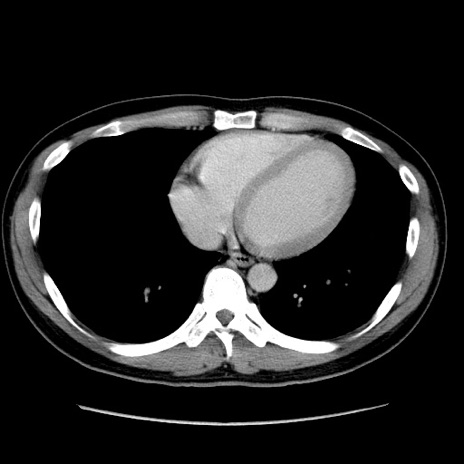

症例4(横断像)

【症例】30歳代男性

【主訴】腹痛、嘔吐

【現病歴】昨晩から突然の腹痛あり、その後嘔吐、軟便も出現。腹痛が改善しないため救急搬送となる。2日前にしめ鯖の食事歴あり。

【身体所見】意識清明、苦悶様、BP 135/90mmHg、BT 35.7℃、腹部:平坦、やや硬、心窩部〜臍部に自発痛、圧痛あり、筋性防御+、反跳痛-

【データ】WBC 8100、CRP 0.57